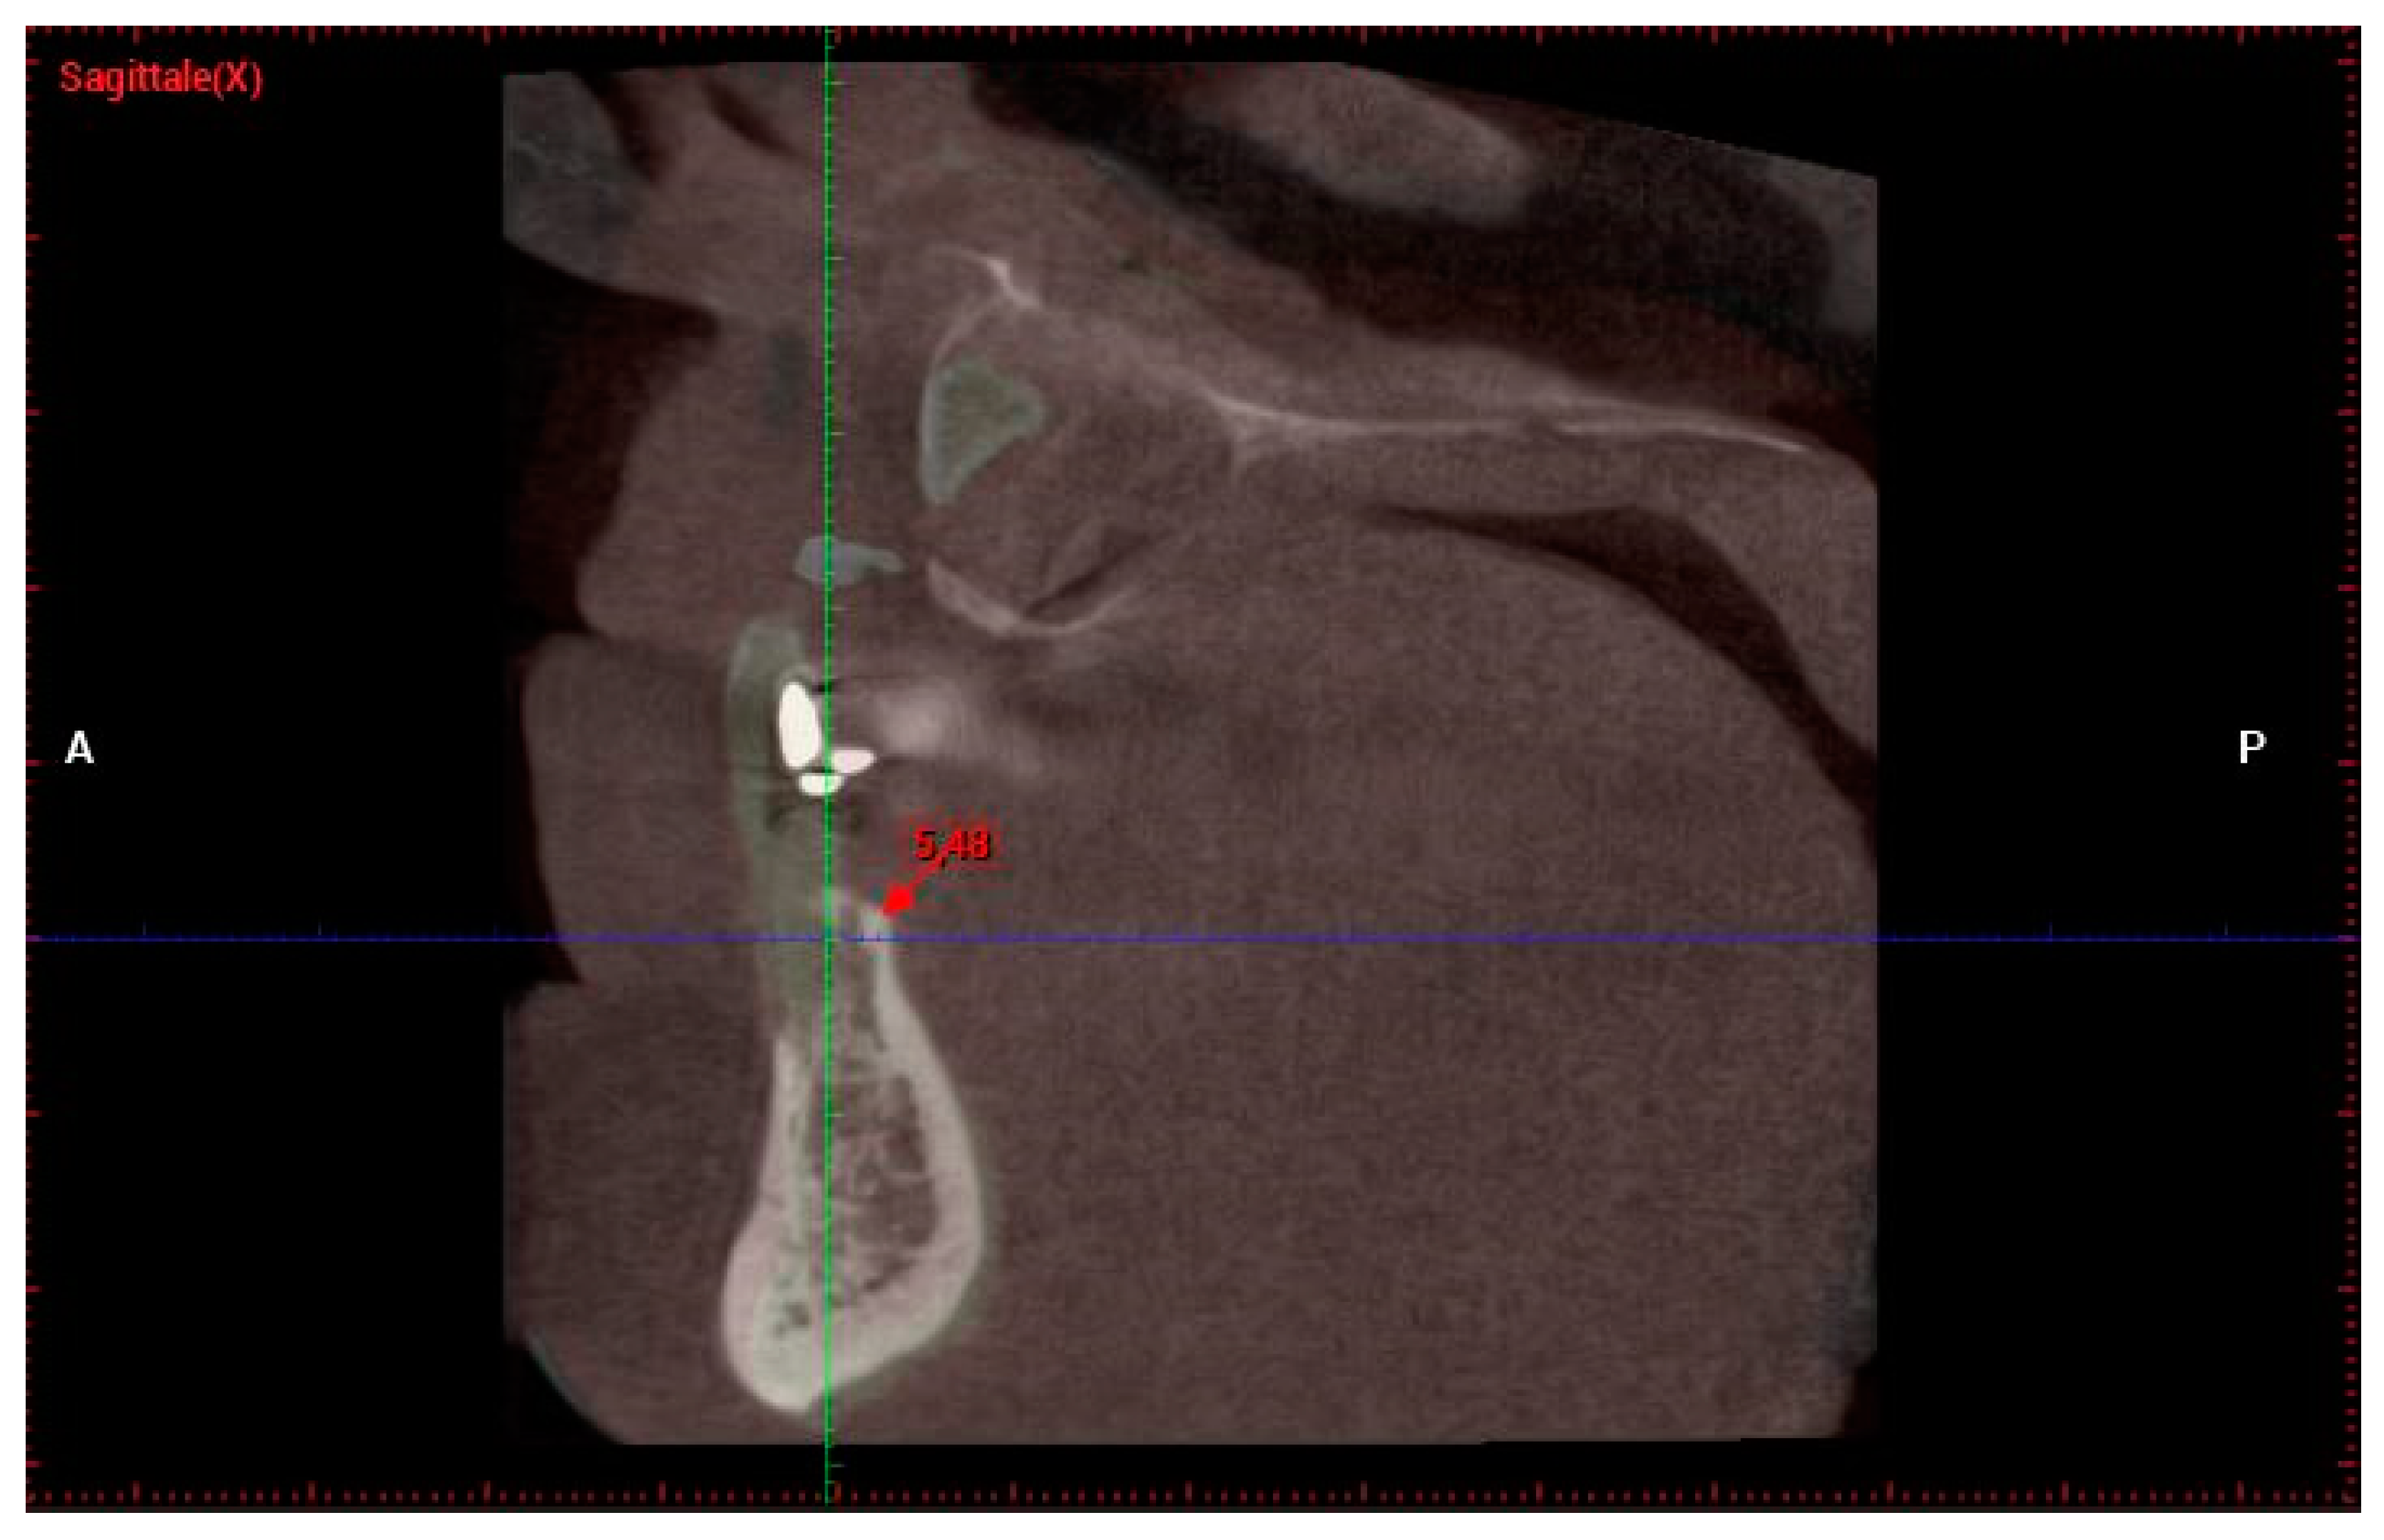

| J.C.—72 | J.C. | 43 | 2 | EXTR 4F | 4 mm | 4 min | 6.82 | 5.48 |